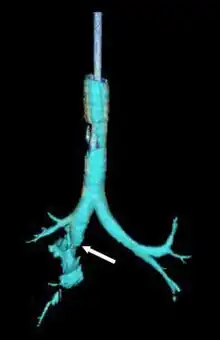

| Reconstruction of the trachea and bronchi with x-ray computed tomography showing disruption of the right main bronchus with abnormal lucency (arrow)[1] | |

Chest x-ray is the initial imaging technique used to diagnose TBI.[17] The film may not have any signs in an otherwise asymptomatic patient.[15] Indications of TBI seen on radiographs include deformity in the trachea or a defect in the tracheal wall.[17] Radiography may also show cervical emphysema, air in the tissues of the neck.[2] X-rays may also show accompanying injuries and signs such as fractures and subcutaneous emphysema.[2] If subcutaneous emphysema occurs and the hyoid bone appears in an X-ray to be sitting unusually high in the throat, it may be an indication that the trachea has been severed.[4] TBI is also suspected if an endotracheal tube appears in an X-ray to be out of place, or if its cuff appears to be more full than normal or to protrude through a tear in the airway.[17] If a bronchus is torn all the way around, the lung may collapse outward toward the chest wall (rather than inward, as it usually does in pneumothorax) because it loses the attachment to the bronchus which normally holds it toward the center.[6] In a person lying face-up, the lung collapses toward the diaphragm and the back.[23] This sign, described in 1969, is called fallen lung sign and is pathognomonic of TBI (that is, it is diagnostic for TBI because it does not occur in other conditions); however it occurs only rarely.[6] In as many as one in five cases, people with blunt trauma and TBI have no signs of the injury on chest X-ray.[23] CT scanning detects over 90% of TBI resulting from blunt trauma,[3] but neither X-ray nor CT are a replacement for bronchoscopy.[6]